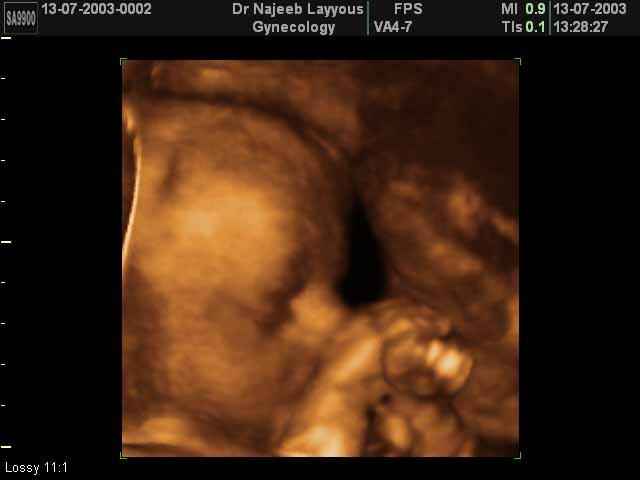

صور جانبية لرأس الجنين بجهاز الالتراساوند ثلاثي الأبعاد | الدكتور نجيب ليوس